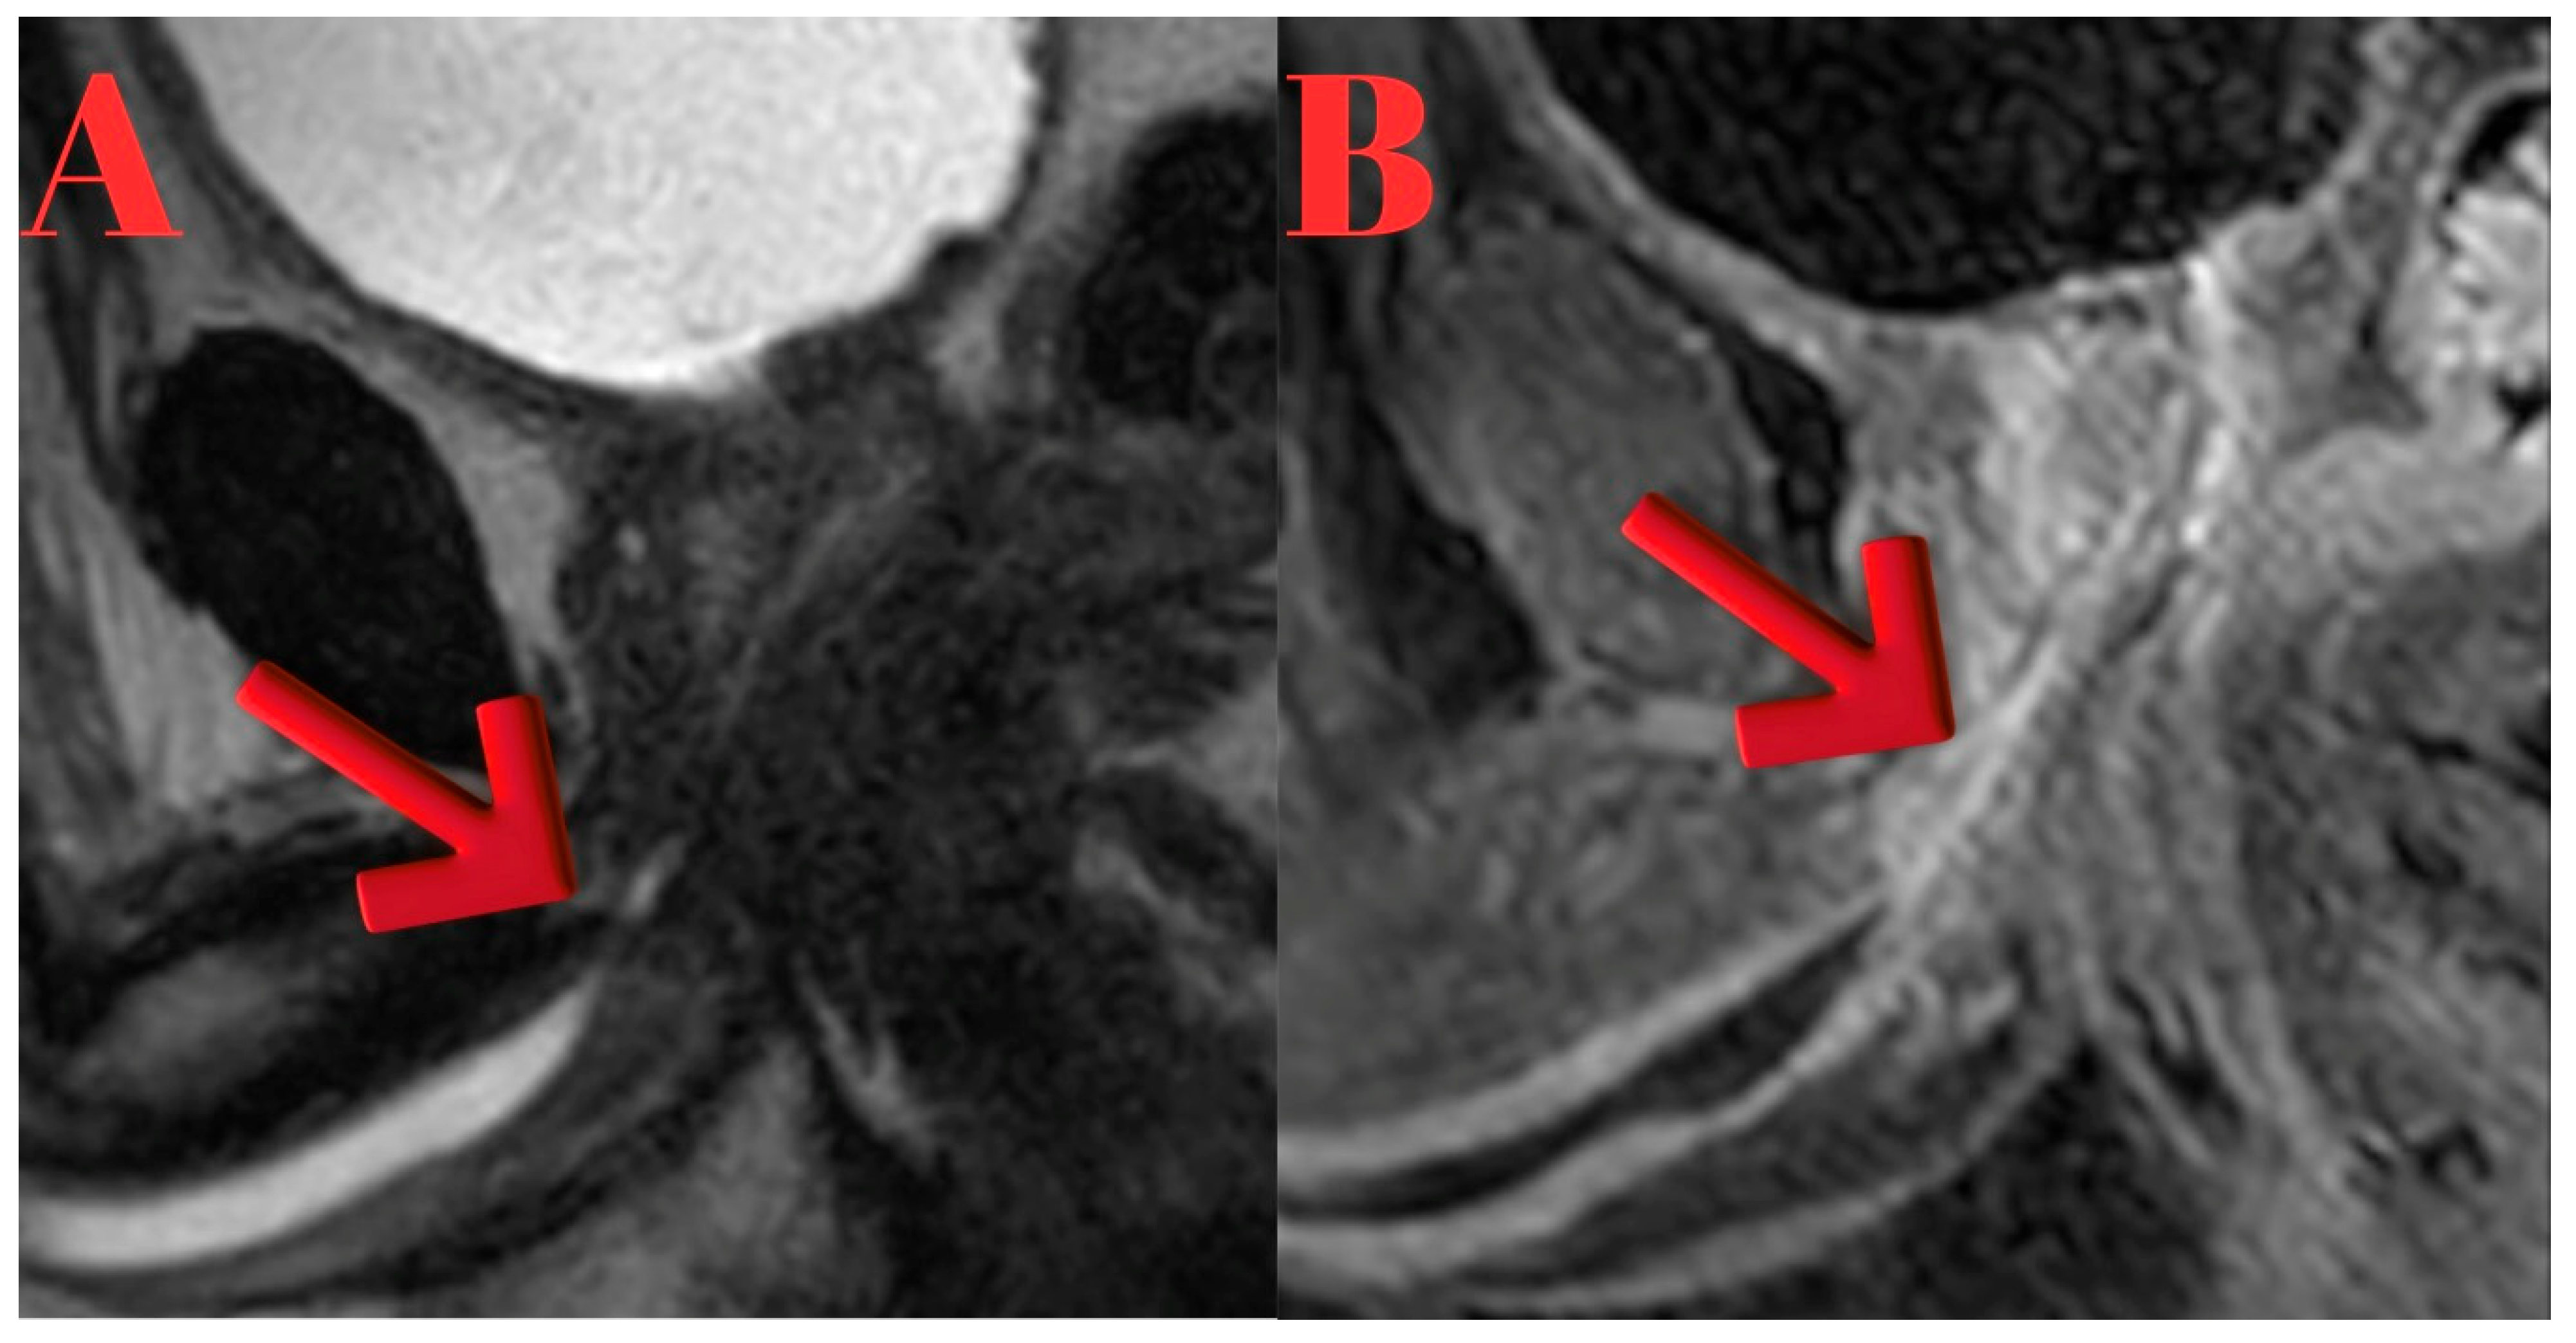

Five months after the accident, a urethral MRI revealed a focal stenotic-occlusive lesion in the penile urethra, approximately 9 cm distal to the urethral meatus. Proximal to the lesion, a localized dilation of up to 6 mm was observed in the penile urethra, with no other abnormalities noted in the remaining urethra (Figure 7).

Figure 7. Sagittal T2-weighted MR images of Case 4. The completely obliterative anterior urethral stricture (arrow) is demonstrated at ~9 cm from the meatus. Two adjacent slices are presented to illustrate the precise location and extent of the stenotic segment, with preserved proximal urethra.